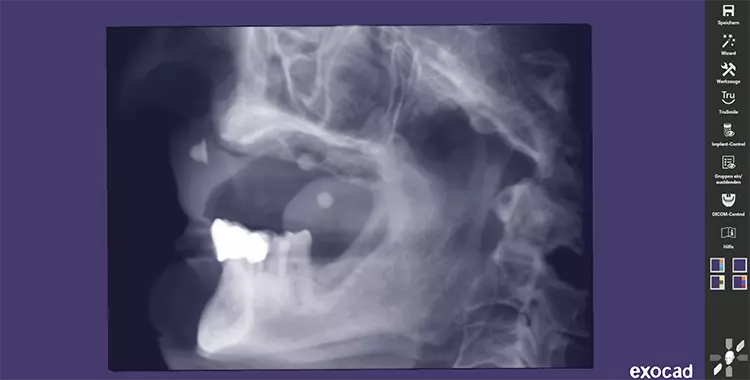

Nach einer Beratung und Aufklärung über Therapieoptionen und -alternativen wurde im gemeinsamen Konsens mit dem Patienten eine Pro-Arch-Sofortversorgung mittels Straumann® BLX im Oberkiefer geplant. Präoperativ wurde die Implantatversorgung mit Hilfe der dreidimensionalen Volumentomographie geplant (Abbildung 2). Die definitive Versorgung erfolgte in Zusammenarbeit mit den Kollegen der Prothetik in domo.

Hierzu wurde eine digitale Planung des Zahnersatzes im Sinne eines Backward Planning erstellt (Abbildung 3 und 4). Nachdem eine digitale Volumentomographie (DVT) des Patienten mit dem vorhandenen Zahnersatz in Okklusion inklusive Referenzpunkten und zusätzlich eine DVT der Prothese extraoral durchgeführt wurde, konnten im Anschluss mit dem Programm Exoplan® beide Scans gematcht werden. Auf dieser Grundlage wurden die sechs Implantate virtuell in idealer Position unter Berücksichtigung des ortsständigen Knochens geplant.

Die Vermeidung einer Sinusbodenelevation, sowie ein maximal großes Unterstützungspolygon standen im Fokus der präoperativen Planung für die festsitzende prothetische Versorgung. Dabei ergab sich ein 17 bzw. 30 Grad Neigungswinkel der distalen Implantate, der durch die Mesostruktur der Multi-unit Abutments ausgeglichen werden sollte, um eine gemeinsame Einschubrichtung für die geplante provisorische Brückenversorgung zu ermöglichen.